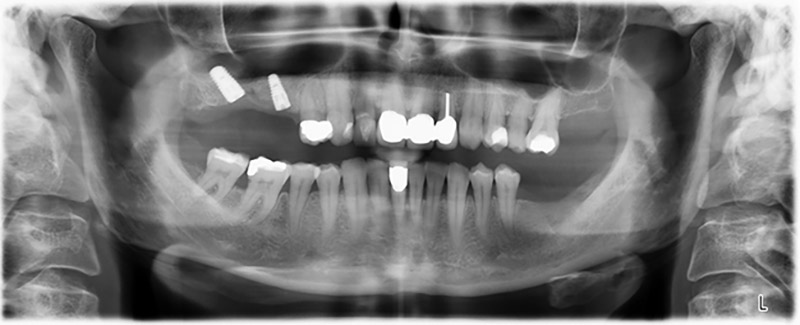

Unos seis meses después de la extracción de las piezas 16 y 14 se realizó una tomografía digital de volúmenes (DVT, Planmeca) para realizar una planificación adecuada y reducir los riesgos al mínimo. En este punto se constató que el hueso no se había regenerado en la cantidad deseada (figuras 2 a 7).

Con el fin de garantizar una restauración fija en al menos dos implantes, era preciso realizar una elevación del suelo del seno maxilar, tanto en la región 16 como en la región 14. Como en este caso la oferta de hueso residual era extremadamente reducida, fue preciso realizar una retirada ósea relativamente grande. Los procedimientos de retirada ósea grande son invasivos y, además, están asociados a una mayor morbilidad del paciente, llevan más tiempo y resultan más costosos. También es más difícil prever los resultados del tratamiento y el riesgo de fracaso es mayor. Teniendo como telón de fondo estas desventajas, la paciente recibió información sobre la posibilidad de utilizar una alternativa extraíble, pero ella la rechazó firmemente.